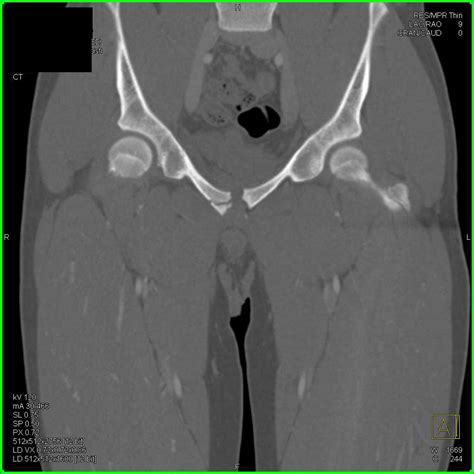

Diagnosing a Ramus Pubic Fracture involves a combination of physical examination and imaging tests. The diagnostic process typically includes:

• Physical Examination: A healthcare provider will assess the pelvic area for pain, swelling, and deformity.

• Imaging Tests: X-rays, CT scans, and MRI scans are commonly used to visualize the fracture and determine its extent.